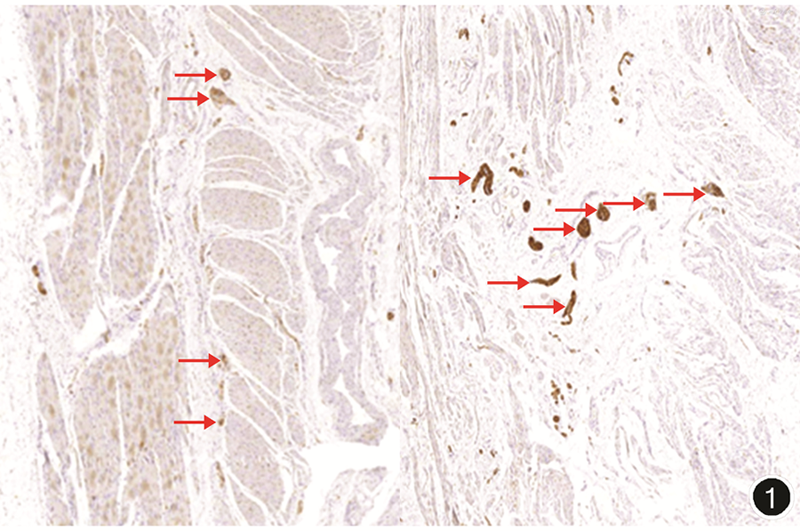

笔者团队自2012年起开展极低位直肠癌功能性保肛相关工作,结果显示:内外括约肌间隙中存在大量神经纤维(图1),经内外括约肌间隙游离后势必导致上述结构的破坏,这与ISR后肛门控便功能紊乱密切相关。在上述亚微解剖基础上,笔者团队率先提出腹腔镜低位直肠癌适形切除功能性保肛手术方式(conformal sphincter-preservation operation,CSPO),其要点在于术中不游离内外括约肌间隙,同时尽可能保留肿瘤对侧正常远端直肠肠壁并在肿瘤对侧肠壁完成吻合,使吻合口尽量远离齿状线(图2),从而在保证肿瘤学安全的同时更好地保护术后肛门功能[7]。此外,多中心回顾性研究进一步证实:与ISR比较,CSPO在保证肿瘤学安全性的同时实现更低位置肿瘤保肛,并显著改善患者术后肛门功能[8]。该手术方式也被《中低位直肠癌手术消化道重建中国专家共识(2021版)》推荐,并被纳入《上海市直肠癌腹腔镜外科手术临床应用管理规范》中直肠癌腹腔镜外科手术参考目录名录。因此,对于超低位直肠癌是否一定要游离到括约肌间沟水平甚至齿状线水平,笔者认为:不赞成为了除肿瘤学安全性以外的因素而进入该区域,应尽可能减少对括约肌本身结构或其附近神经末梢的损伤从而保护肛门功能。